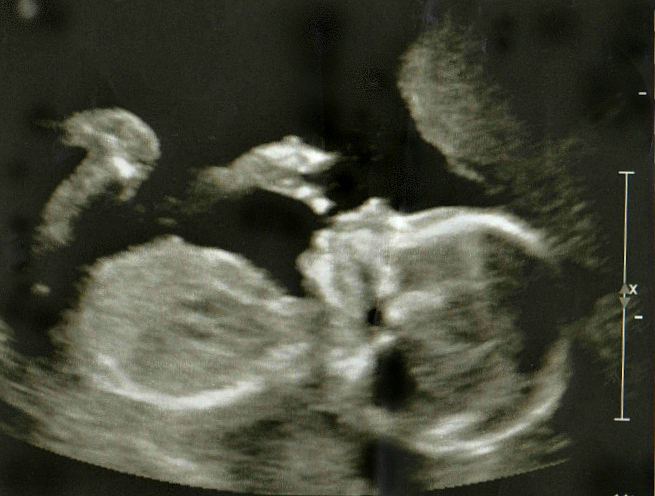

Savannah Hope, 19 Weeks

Savannah Hope, 19 Weeks – Stomach Inside Chest

Severe CHD is determined when the contents of the abdomen are in the chest or ‘liver-up.’ It affects about one in every 2,500 live births per year. The black mass in her chest is her stomach pressing against her heart. Oh, our sweet a baby girl!? Our routine ultrasound went from a moment of joyous celebration to the scariest moment of our lives.